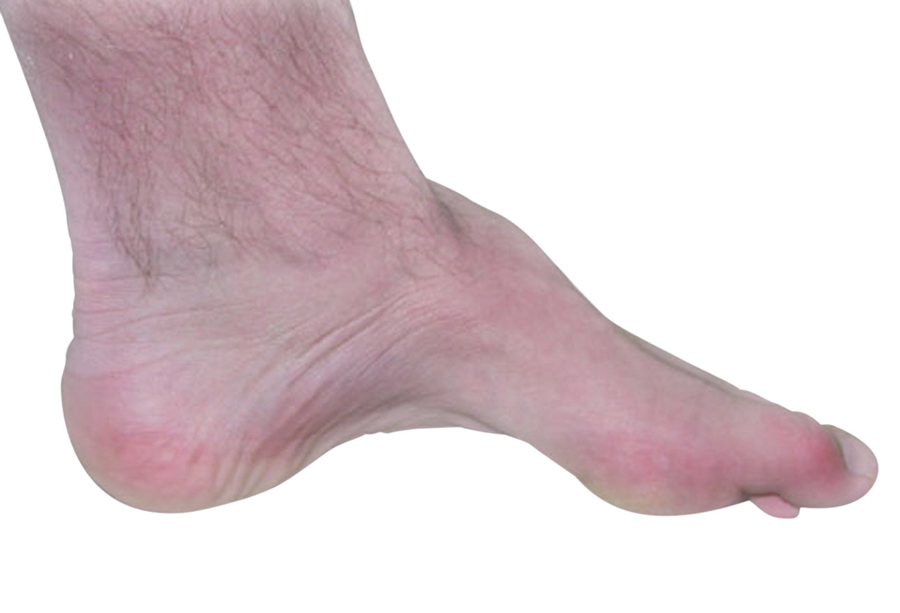

20岁男性,足弓高(如图所示),由于近期行走困难、脚趾频繁碰到地面导致跌倒而就诊。患者家族中也有过类似症状的亲属,患者的兄弟的腿有类似鹤腿状的表现。体格检查中,患者姿势和步幅都是正常的,然而在行走过程中,由于足部下垂,足部的过度抬高显而易见。

腓骨肌萎缩症是最常见的遗传性神经系统疾病。腓骨肌萎缩症1型是一种脱髓鞘性神经病,表现为慢性进展性远端无力、肌肉萎缩和感觉丧失。2型为轴索型,发病通常较晚,肌萎缩症状及出现部位与1型相似,而程度较轻。

在此类患者中,典型的步态异常是跨阈步态和足下垂,姿势和步幅是正常的。试图走路时,患者必须把腿抬高以让脚离地,脚随后以拍打的方式撞击地面。通常在腓神经病变或L5神经根损伤的情况下可以观察到单侧足下垂。双侧足下垂可以见于严重的多发性神经病和前角细胞疾病,如脊髓性肌萎缩